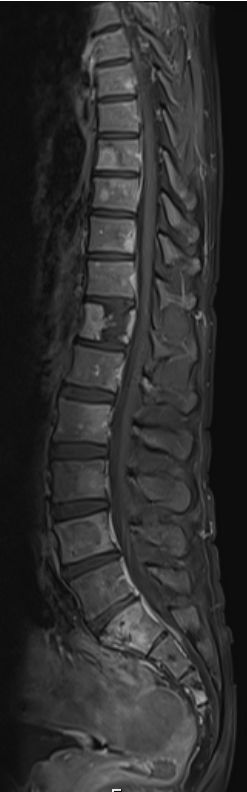

| Knochen | 36-jähriger Mann, der vor 2Jahren wegen eines blutenden "Ulkus" übernäht wurde.

Jetzt fortgeschrittenes Magenkarzinom. Gastektomie, Lymphonodektomie, Splenektomie,Ösophagojejunostomie,Y-Roux -Anastomose nach FLOT -Chemotherapie.

Das MRT zeigt Wirbelmetastasen.![]() |